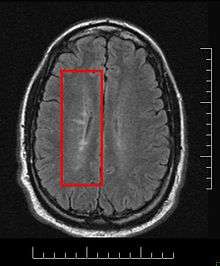

Due to the distribution of the lesions, since 1916 they are also known as Dawson's fingers.[44] They appear around the brain blood vessels.

Lesions under MRI

Most MS lesions are isointense to white matter (they appear bright) on T1-weighted MRI, but some are "hypointense" (lower intensity). These are called "black holes" (BH). They appear specially in the supratentorial region of the brain.

When BH's appear, around half of them revert in a month. This is considered a sign of remyelination. When they remain, this is regarded as a sign of permanent demyelination and axonal loss. This has been shown on post-mortem autopsies.[97]

The lesion evolution under MRI has been reported to begin as a pattern of central hyperintensity. This was seen in the majority of new lesions, both on proton density and contrast-enhanced T1-weighted images.[99] When gadolinium is used, the lesion expansion can be classified as nodular or ringlike[100]